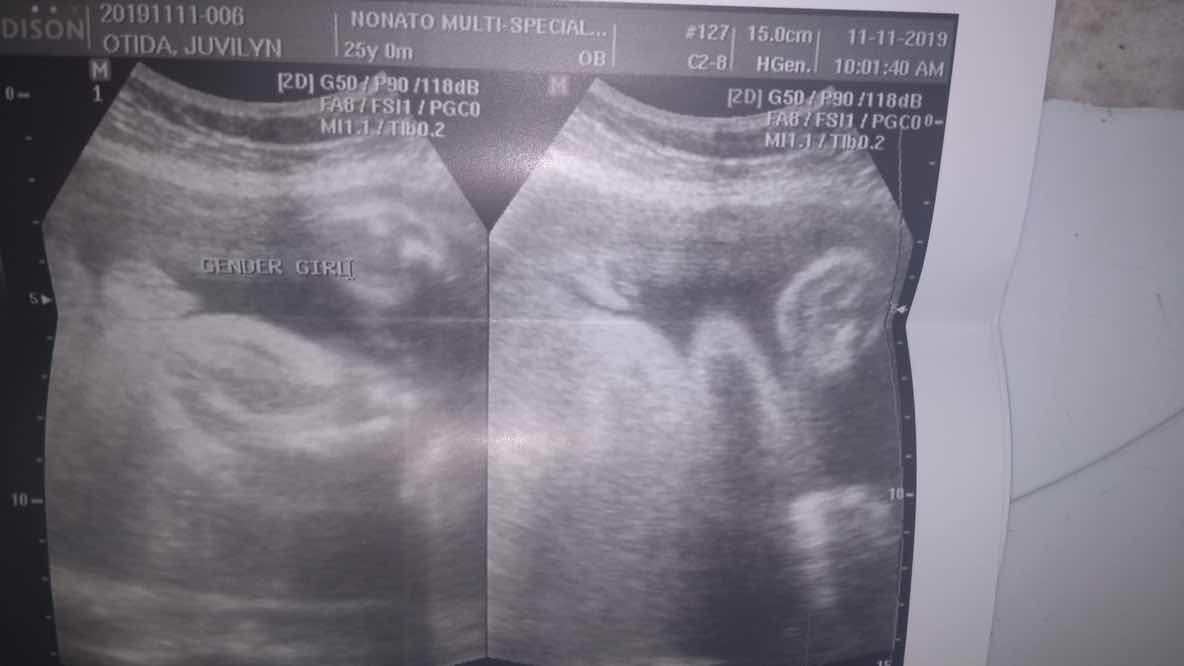

Im on my 32 week of pregnancy. First utz ko was nung 5 mons pako, that time malinaw yung result kasi mejo mahal. Nakita ko yung face, muka talagang boy kaso di maconfirm kasi nakabreech sya. Ngayong 8 months nako, ito yung result, sobrang labo kahit nung actual ultrasound, sabi pa nung nag utz nahirapan daw sya makita. But she still say its a baby girl. Pero di ko talaga maimagine haha Dont get me wrong , im still happy if its a girl kasi may minime ako hahaha pero since 5 mons umaasa talaga ako na boooy, and wala pang boy sa family namin kaya we are hoping. Any thoughts mga mommy?